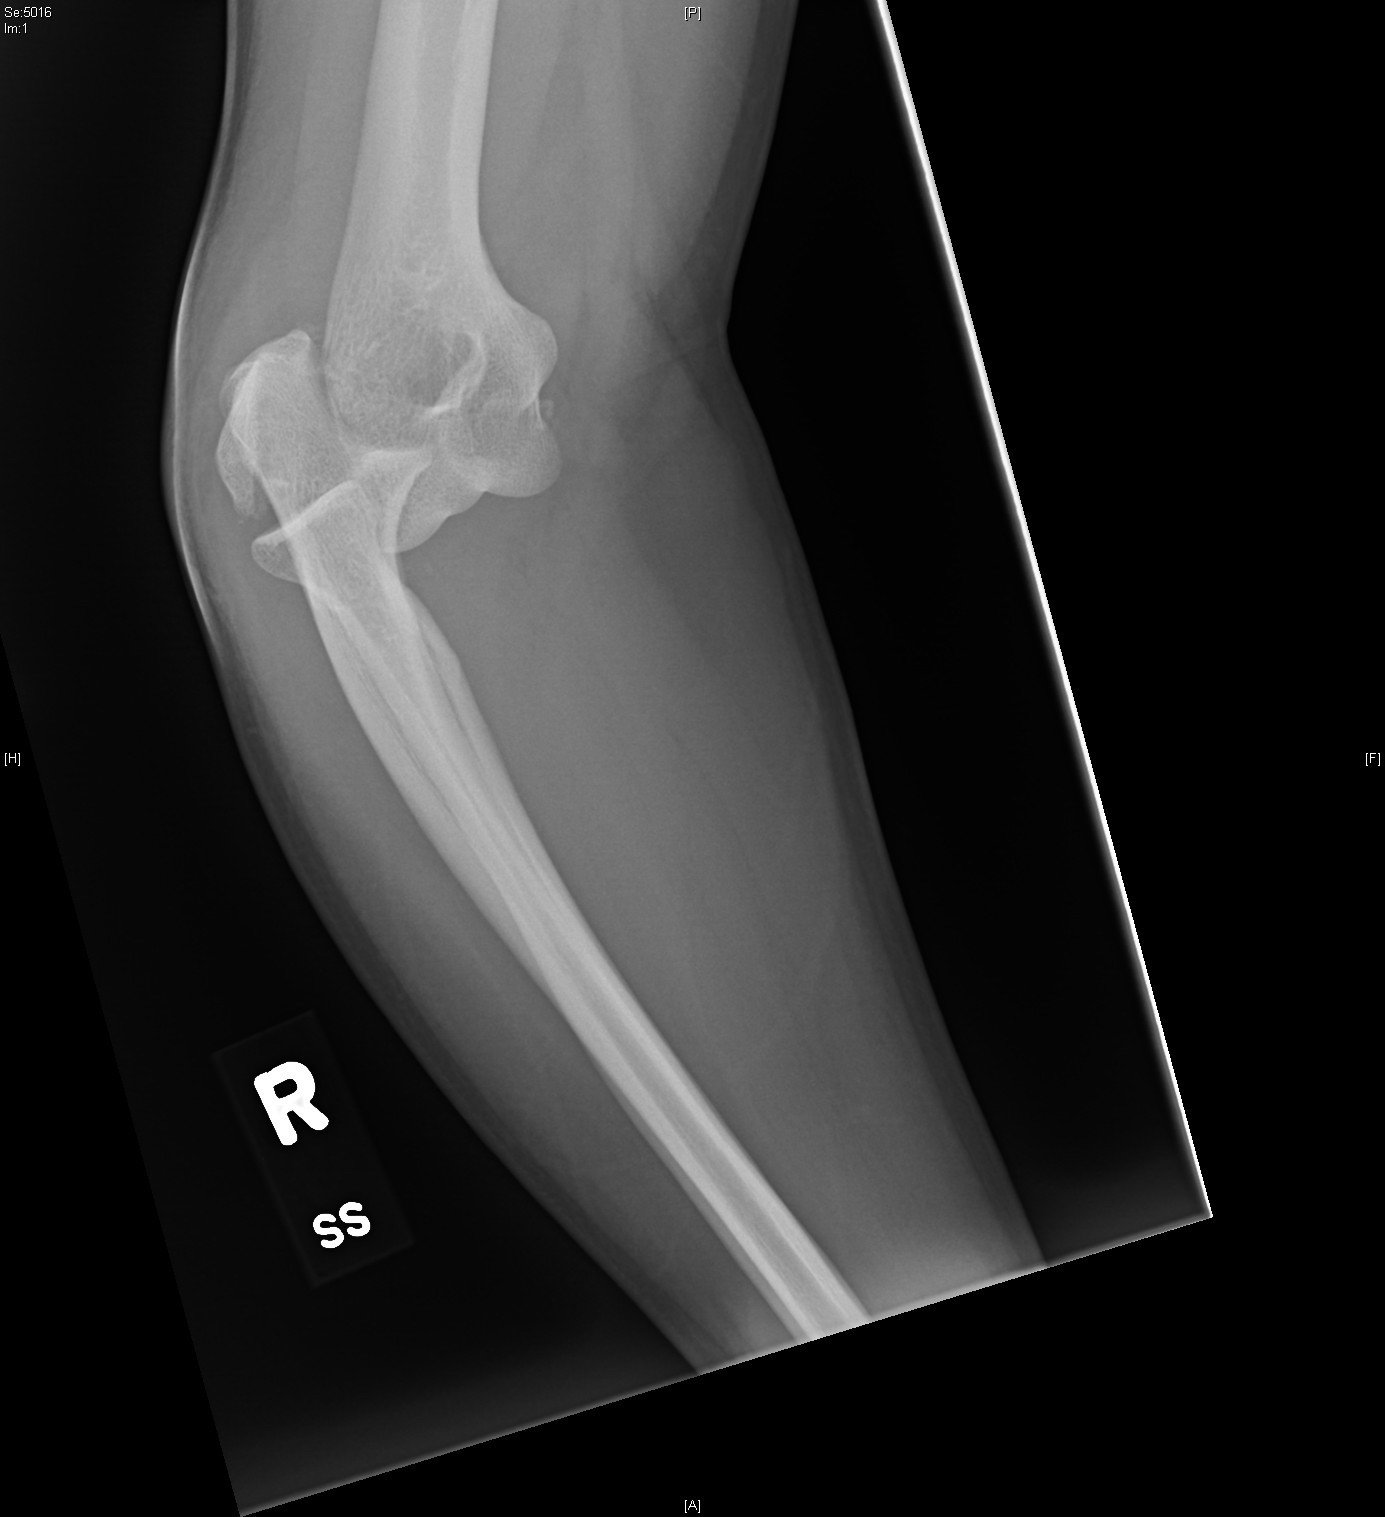

Radiographs of the right elbow revealed an acute fracture through the lateral epicondyle with dislocation of the radial head inferiorly. Radiographs of the left elbow revealed a slightly angulated fracture through the lateral epicondyle.

Given the patient’s bilateral condylar fractures, orthopedics was consulted and recommended reduction of the dislocated right radial head with bilateral splinting. Post-reduction films revealed successful reduction and patient was neurovascularly intact before and after the procedure. The patient was discharged with instructions for short interval follow up in the orthopedics clinic to discuss the necessity for surgical management of the fractures.